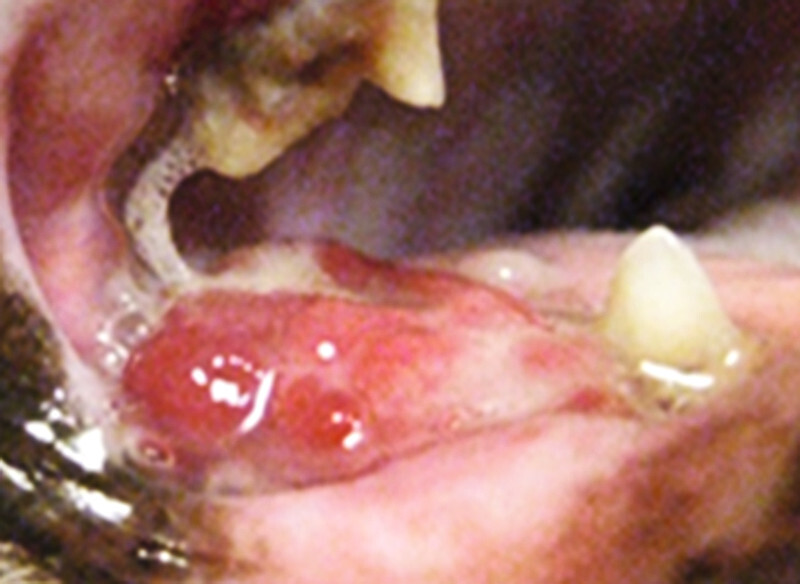

Orale Plattenepithelkarzinome (PEC) können gingival, sublingual und tonsillär lokalisiert sein, wobei die gingivale Form als das häufigste orale PEC der Katze sowohl maxillär als auch mandibular auftritt. Das Wachstum ist infiltrativ und Metastasen finden sich eher selten [6] . Die vorliegende ausgeprägte Osteolyse imponiert meist bereits bei der Diagnosestellung [3] und typischerweise werden beim gingivalen Plattenepithelkarzinom gelockerte Zähne beobachtet. Gerade dann, wenn bei Katzen Zähne gelockert oder „leicht“ zu extrahieren sind, ist besondere Aufmerksamkeit geboten und entsprechende Kieferabschnitte sollten unbedingt röntgenologisch untersucht werden. Begleitende orale Entzündungen können einerseits Tumore maskieren, während andererseits proliferative Entzündungen das Vorliegen eines Tumors vortäuschen können ( [Abb. 1] und [2] ).

Sublinguale Plattenepithelkarzinome sind auf Grund ihrer Lokalisation für Tierbesitzer besonders schwer zu entdecken ( [Abb. 3] ). In frühen Stadien wird die Zunge betroffener Katzen unbeweglicher und aufmerksame Besitzer bemerken mitunter ein verändertes Fressverhalten. Therapeutisch kommt auch hier am ehesten eine multimodale Therapie infrage, da ein ausschließlich chirurgisches Vorgehen bei sublingualen Plattenepithelkarzinomen – außer in sehr frühen Stadien – meist nicht möglich ist.